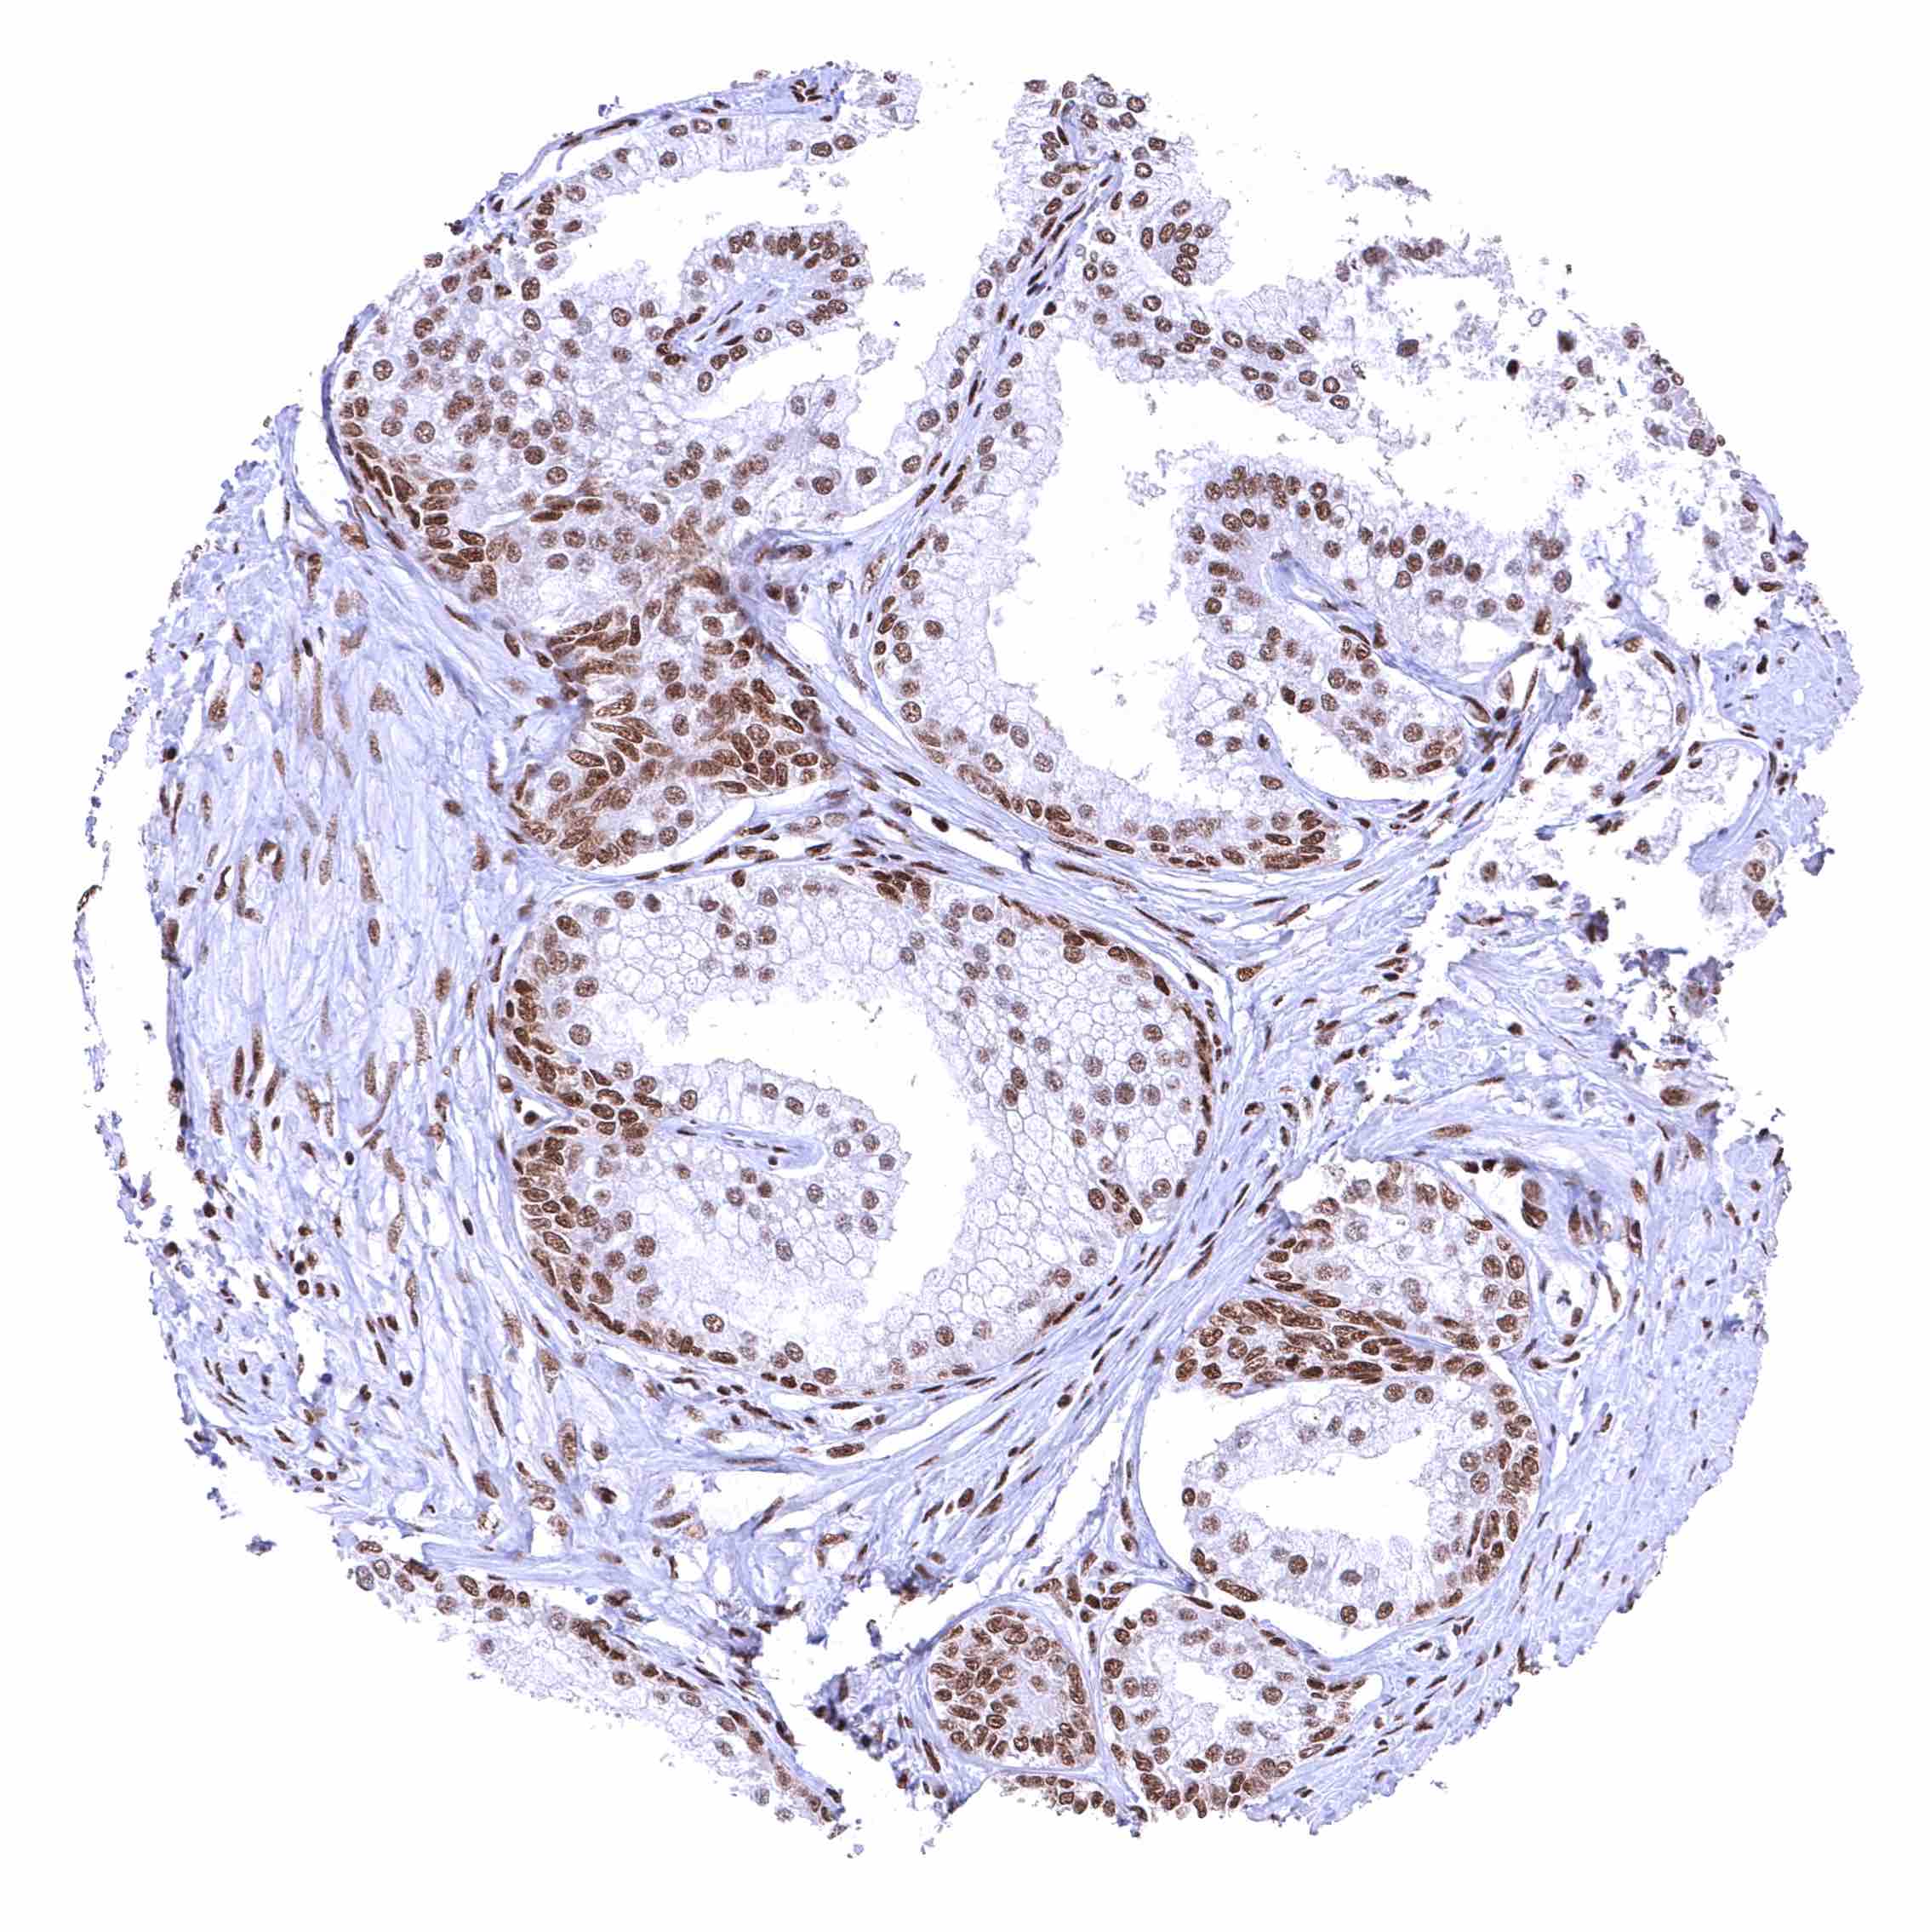

Prostate – BRD4 staining of basal cells is somewhat stronger than of acinar cells.